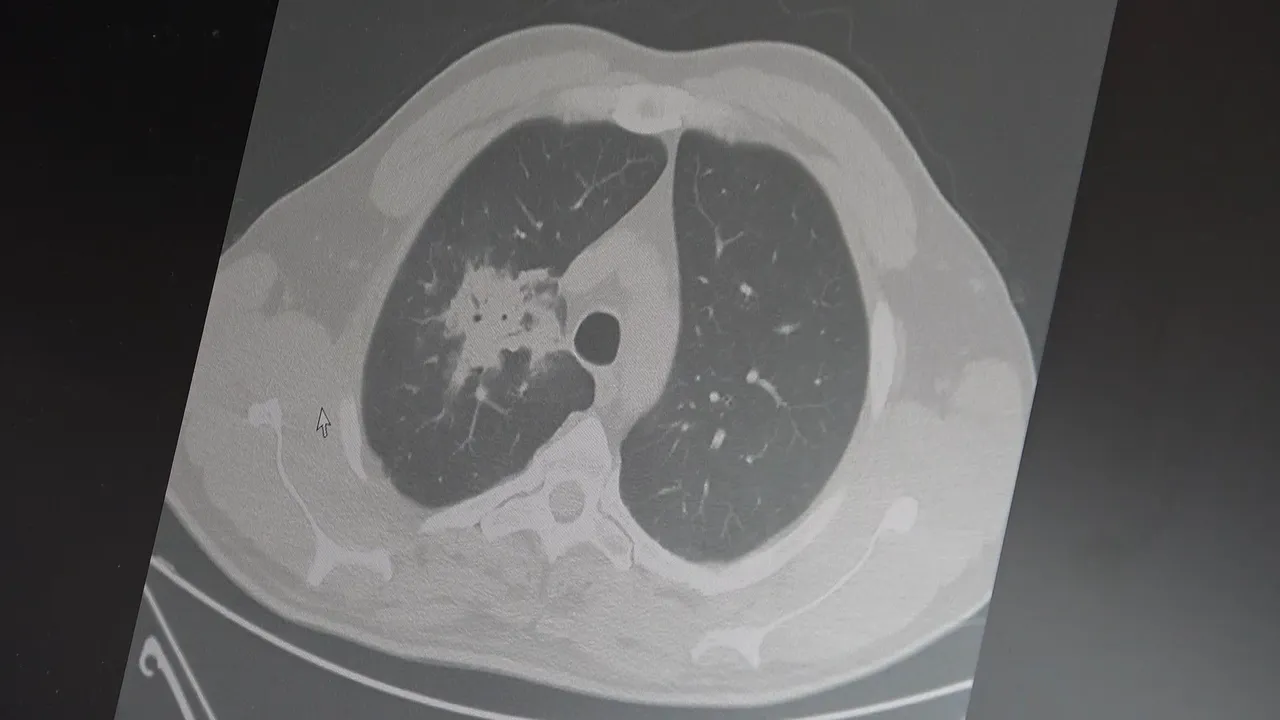

100'den fazla bilimsel çalışmanın incelendiği kapsamlı analizlere dikkat çeken Özkaya, elektronik sigaraların özellikle temas ettiği akciğer ve ağız bölgelerinde kanser riskini artırabileceğine dair güçlü bulgular bulunduğunu belirtti.

2024 yılında yayımlanan bir çalışmaya da değinen Özkaya, hem geleneksel sigara hem de elektronik sigara kullanan bireylerde akciğer kanseri riskinin, sadece sigara içenlere göre dört kat daha fazla olduğunun bildirildiğini kaydetti.